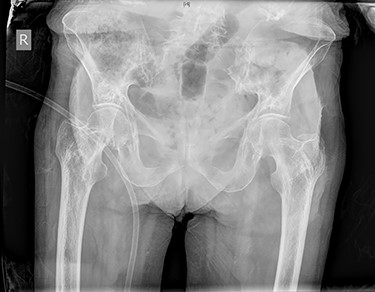

On presentation her vital signs were within normal limits including heart rate 67 beats per minute, blood pressure 145/67 mmHg, respiratory rate 22, temperature 36.2°C and SpO2 100% on nasal prongs (2 L/min). Her abdomen was soft with no palpable masses and normal bowel sounds. The right groin pain was exacerbated by extension and abduction of the right hip and tenderness over the medial adductors. Initial biochemical investigations, including full blood count, electrolytes, renal function, liver function and coagulation panel were normal. A pelvic X-ray did not show any features of fracture or bowel obstruction (Fig. 1). The initial differential diagnoses included adductor strain and occult fracture of the right hip. She was admitted under geriatrics for treatment of constipation and mobility assessment during which time her bowels opened.

Pelvic X-ray on initial admission demonstrated no features of fracture, bowel obstruction or incarcerated hernia.